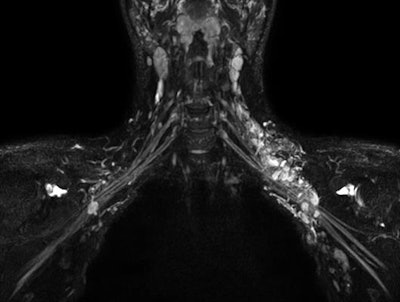

Ingenia Ambition MRI with 3D NerveView can help visualize the brachial and lumbar plexus with a high-resolution T2-weighted, turbo spin-echo acquisition with reduced remaining intralumen signal of the veins. Image courtesy of Philips Healthcare.The Easy Switch feature allows for quick deactivation of the BlueSeal magnetic field if something should be stuck in the bore. Once the problem is resolved, an in-house or Philips technician can begin an automated start to bring the magnet back online. In addition, the Ingenia Ambition's SmartExam analytics allows for automatic planning, scanning, and processing, which is designed a single operator to manage the full MRI scan from the patient's side with the touch of one button.